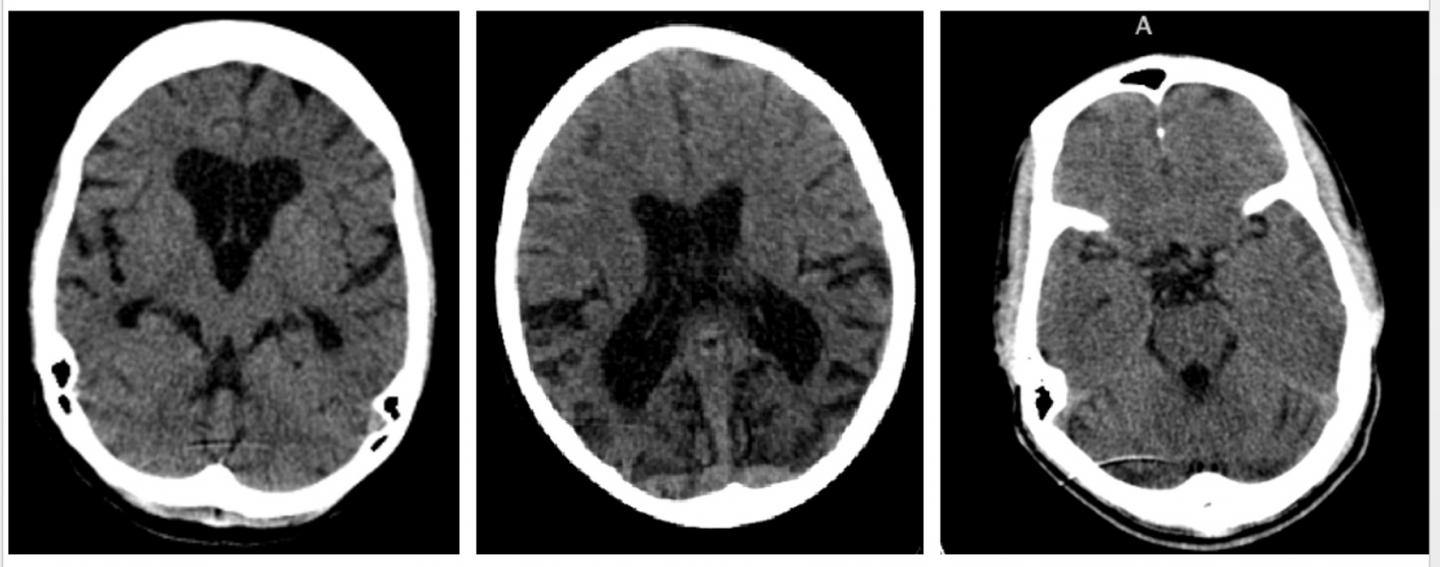

Selected patients were invited to attend a joint neuro-psychiatric clinic where they underwent a full neurological examination, psychiatric screening and specialist investigations including brain scan imaging.